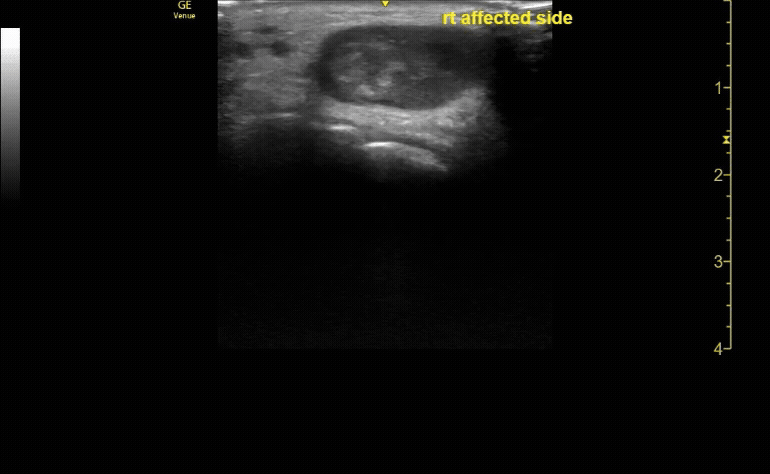

Sagittal view of achilles tendon rupture.

c/o Jasmine Hill, MD